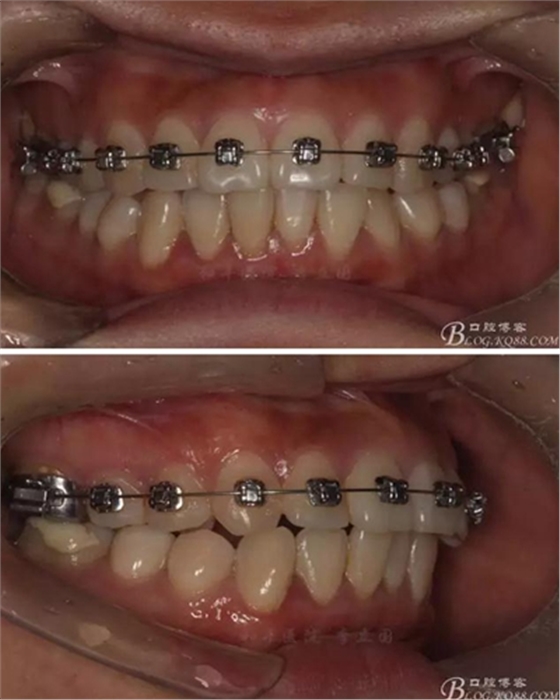

鎖合矯治思路:

1、最常用的當屬交互牽引,不適用于磨牙伸長、高角病例,但鎖合一般都伴有磨牙的伸長,所以交互牽引雖然簡單,但并不是最佳的治療方法。

2、種植支抗,所有的鎖合種植支抗基本都能解決,但其應(yīng)用受到醫(yī)生的技術(shù)水平及患者的接受程度的限制。